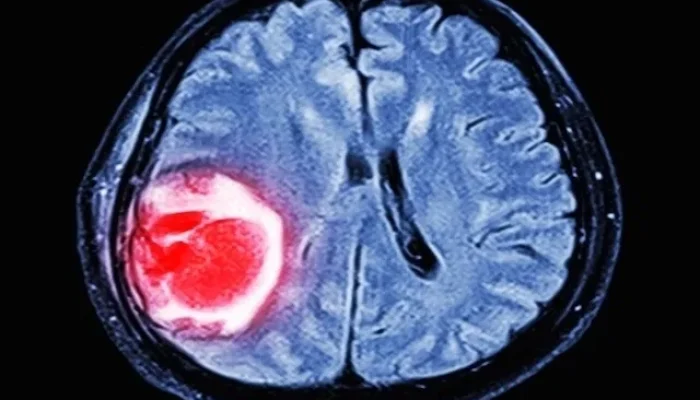

Cistos Cerebrais: Entenda Quando a Descoberta Pede Acompanhamento ou Intervenção